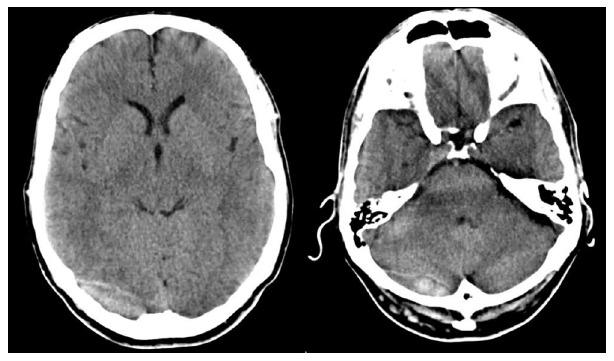

Dural sinus thrombosis following a head trauma is a rare condition, described in literature along with the lack of consensus regarding diagnosis and management. We present a case of a fifty-year-old man with a head injury and combined supratentorial-subtentorial epidural hematoma who was treated conservatively through the administration of low molecular weight heparin. The diagnosis and management of this condition are discussed based on a literature review. The early diagnosis may prevent potentially treatable poor outcomes.

Post traumatic dural sinus thrombosis following epidural hematoma: Literature review and case report.